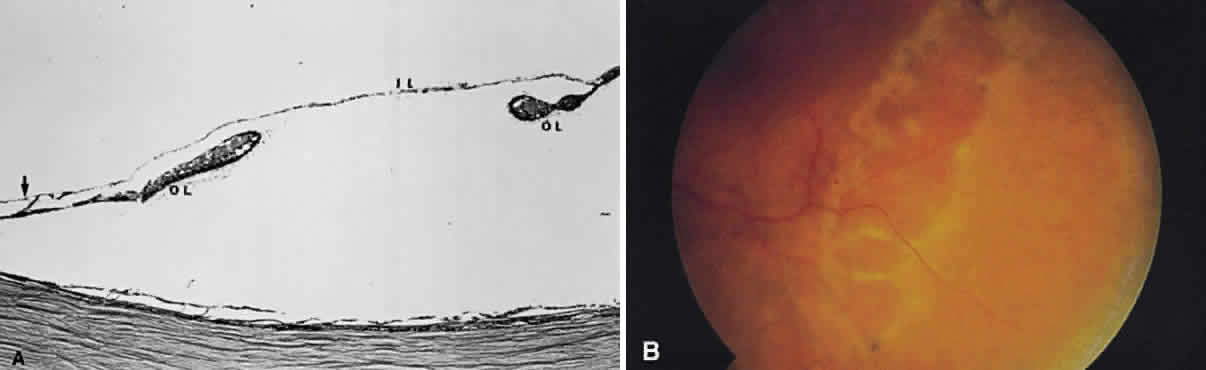

seen in fresh hemorrhages anterior to the pigment epithelium (see Fig. 13A). The location of hemorrhages within the retina also accounts for the shape of the lesion. Blood that accumulates between the nerve fiber layer and

the internal limiting membrane (subinternal limiting membrane hemorrhage) (Fig. 57) assumes a shape defined by gravity, meniscus or boat-shaped, when the

patient is upright (Fig. 58). The name subinternal limiting membrane hemorrhage is technically ambiguous, since

a hemorrhage in the outer plexiform layer also is below (sub) the

internal limiting membrane.  Fig. 57. Photomicrograph of a hemorrhage present just beneath the internal limiting

membrane. The hemorrhage is delimited on the photomicrograph by arrows. Fig. 57. Photomicrograph of a hemorrhage present just beneath the internal limiting

membrane. The hemorrhage is delimited on the photomicrograph by arrows.

|

Fig. 58. Hemorrhage located just beneath the internal limiting membrane with the

patient in the upright position. The retinal vessels are visible on the

surface of the layered hemorrhage. Fig. 58. Hemorrhage located just beneath the internal limiting membrane with the

patient in the upright position. The retinal vessels are visible on the

surface of the layered hemorrhage.